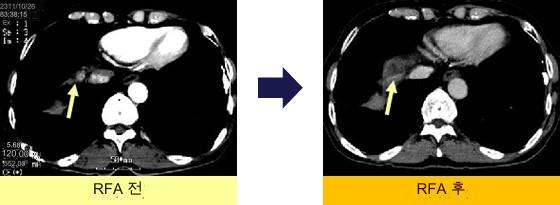

치료 곤란 부위에 대한 RFA

IVC와키돔 아래

돔 아래, IVC 겨드랑이, 심장 겨드랑이 병변.인공 흉수 없음, 체위 변환만으로 RFA 시행.재발 없음.